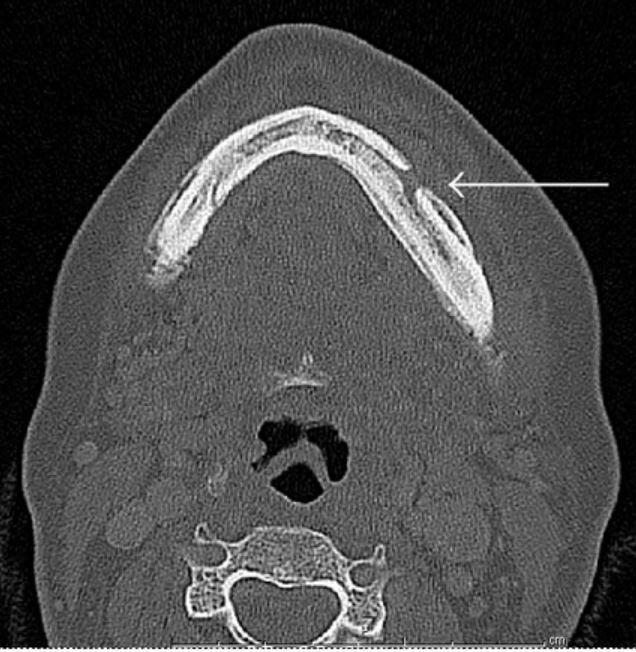

Una tomografía computarizada de una mandíbula con una flecha señalando un área abierta en el hueso.

En esta tomografía computarizada, una flecha marca una osteonecrosis de la mandíbula, que quizás fue a causa del tratamiento con un bisfosfonato.

Fuente: Case Reports in Oncological Medicine. 2014. doi: 10.1155/2014/281812. CC BY 3.0.